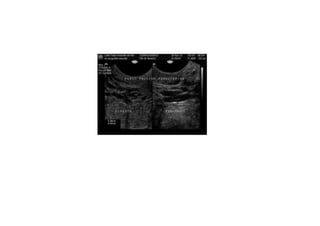

Comment  établir  le  diagnos=que  ?   1.  Par   la   symptomatologie,   en   par8culier   la   douleur  et  la  lourdeur  dans  le  bassin  avec  une   aggrava8on   pendant   la   menstrua8on,   mais   aussi   la   dysménorrhée,   la   dyspareunie,   la   cons8pa8on  et  les  douleurs  lombaires.   2.  Par   la   présence   de   varices   dans   la   région   postérieure   et   latérale   des   cuisses,   dans   les   fessiers  et  les  par=es  génitales.   3.  À   l’aide   d’un   écho-­‐doppler   transvaginal   et   abdominal.

En  rappel:  avant  traitement   Phlébographie  et  echographie  transvaginale   (slide  suivant)

CONCLUSION  :   • La   phlébographie   et   l’embolisa=on   ont   amélioré   significa=vement   la   situa=on   phlébologique   et   clinique   :   dispari8on   de   la   douleur   pelvienne,   de   la   sensa8on   de   pesanteur  dans  les  membres  inférieurs  et  de   la  cons8pa8on  intes8nale   •  Aucune   complica=on   sérieuse   n’a   été   constatée   Kennedy-­‐gp@uol.com.br